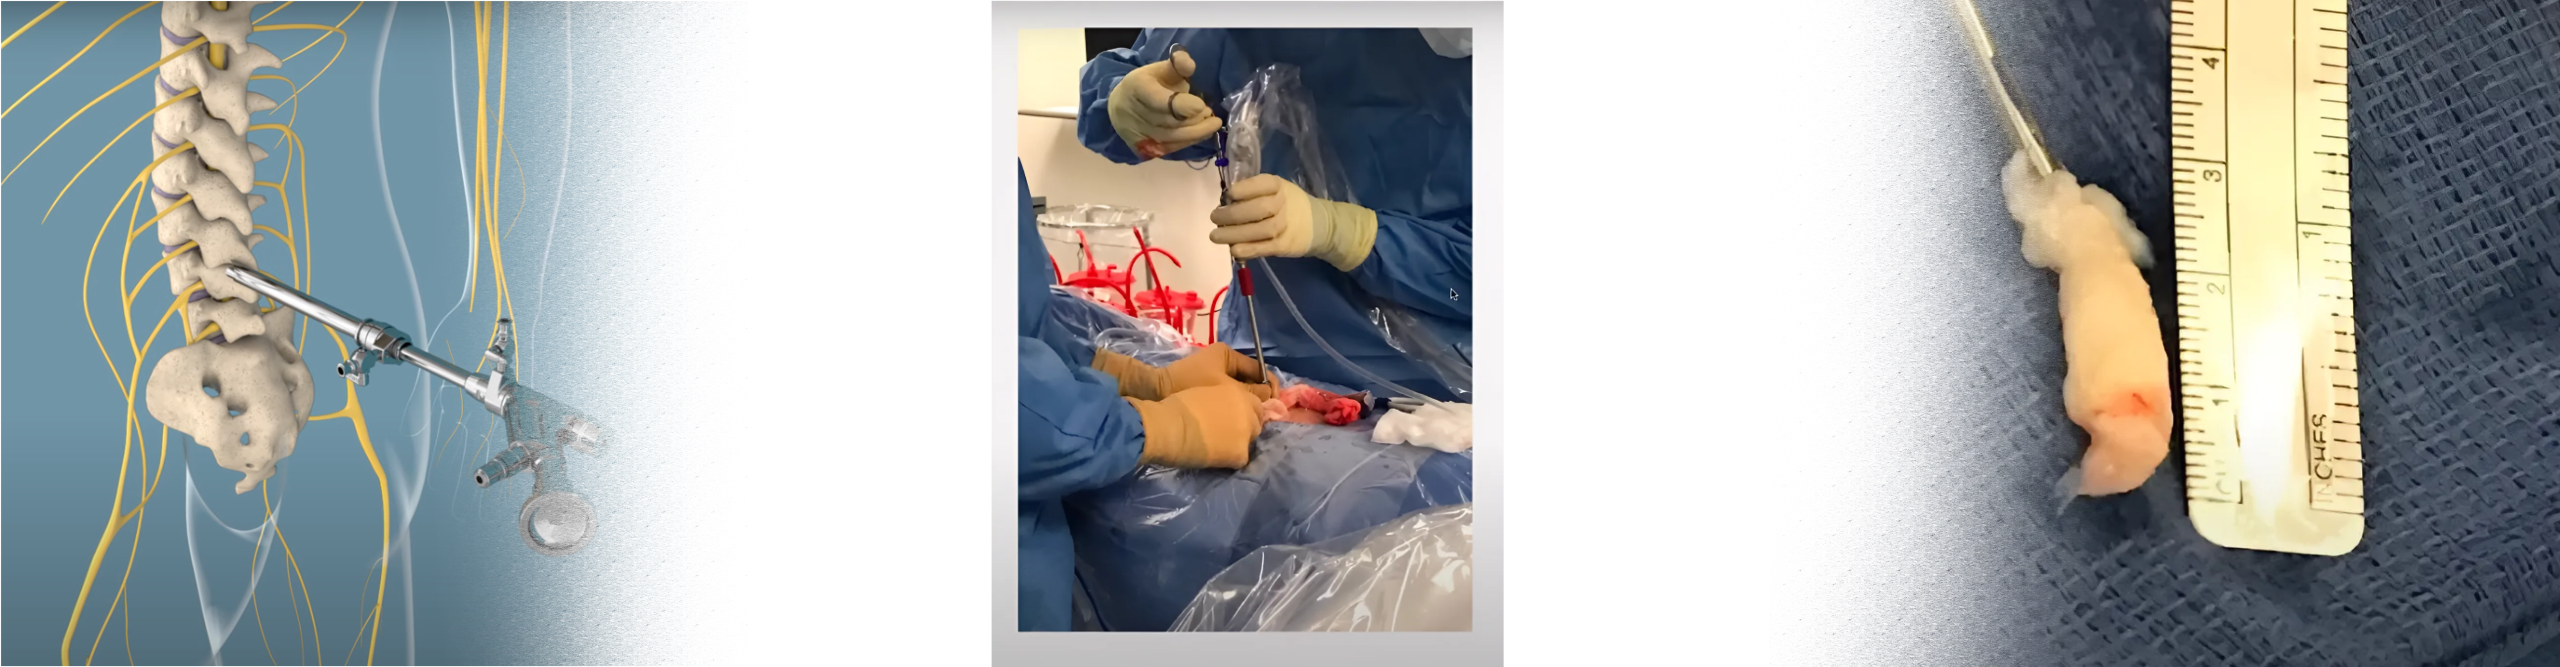

Endoscopic discectomy is a minimally invasive spine surgery procedure used to treat disc herniation in the lumbar spine. The procedure involves accessing the herniated disc through a small incision in the back using an endoscope, a thin tube with a camera and surgical instruments attached. By visualizing the herniated disc on a monitor, the surgeon can precisely remove the herniated portion of the disc, relieving pressure on the spinal nerves and alleviating symptoms such as pain, numbness, and weakness.

Endoscopic discectomy is typically performed under local anesthesia with sedation and involves the following steps:

1. Patient Positioning: The patient is positioned face down on a specialized operating table, allowing access to the lumbar spine.

2. Incision: A small incision (usually less than one cm) is made in the back, directly over the affected disc.

3. Endoscope Insertion: The endoscope is inserted through the incision and guided to the herniated disc under fluoroscopic guidance.

4. Visualization: The surgeon visualizes the herniated disc and surrounding structures on a monitor connected to the endoscope.

5. Discectomy: Using specialized instruments, the surgeon removes the herniated portion of the disc, relieving pressure on the spinal nerves.

6. Closure: No uterus or clips are required. The incision is closed with a surgical glue, and a sterile dressing is applied to the surgical site.